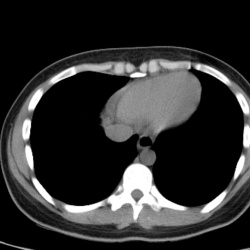

Коллеги помогите разобраться. В отделение ОНМК поступила женищна 72 года, с подозрением на ОНМК, сбор анамнеза затруднен ввиду конгнитивиных нарушений. В крови анемия. Желтушная, умеренно повышены...